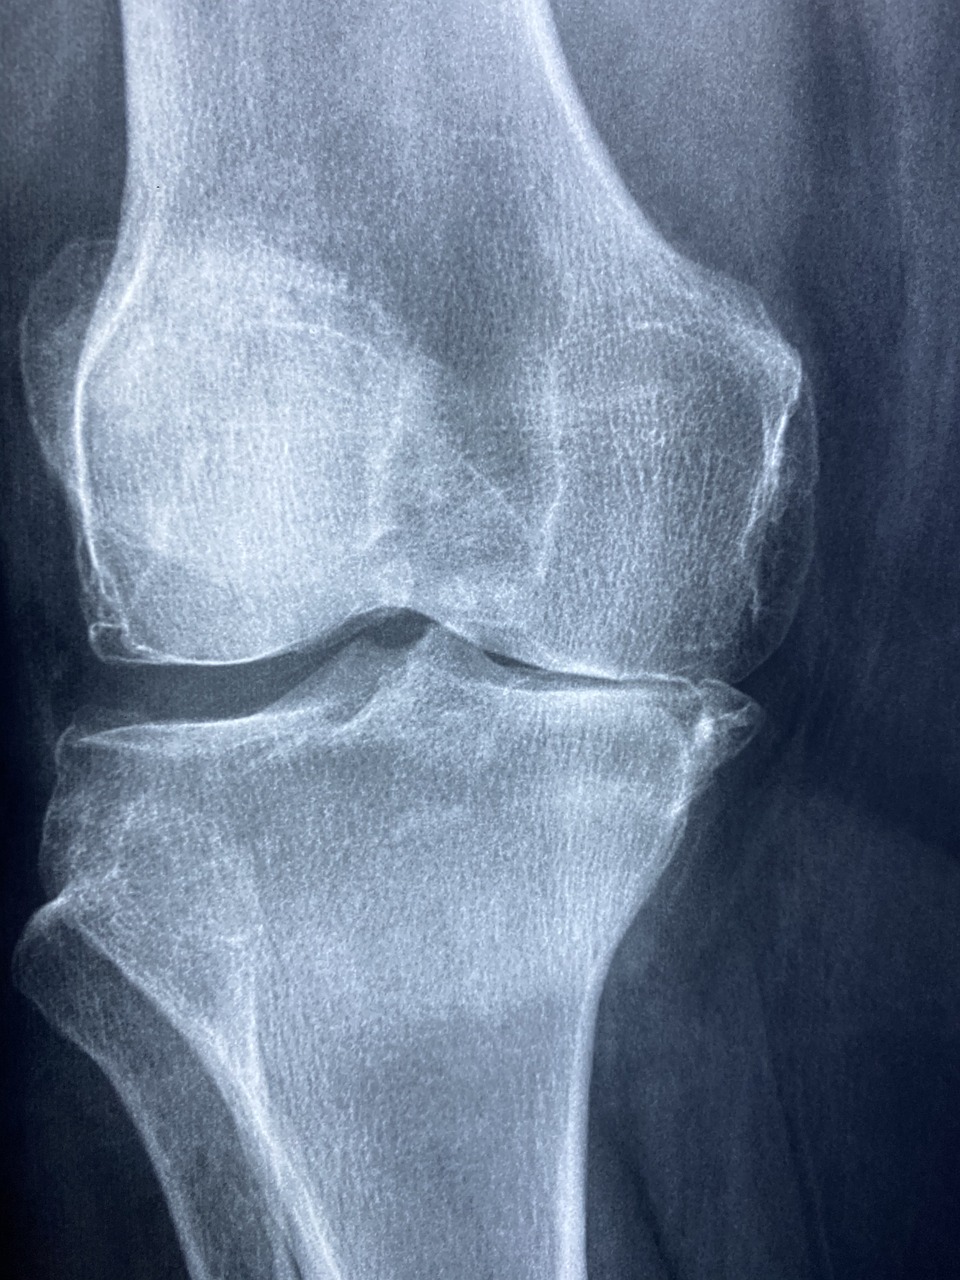

• 퇴행성 관절염(골관절염)

• 주로 노화, 반복적인 관절 사용, 체중 증가 등으로 인해 관절 연골이 점차 닳아 없어지서 발생합니다.

• 연골이 닳으면서 뼈와 인대에 손상이 생기고, 이로 인해 통증과 부종이 나타납니다

• 퇴행성 관절염

• 무릎, 엉덩이, 척추, 손가락 끝마디(원위지간관절) 등 체중 부하가 많은 관절에서 주로 발생합니다